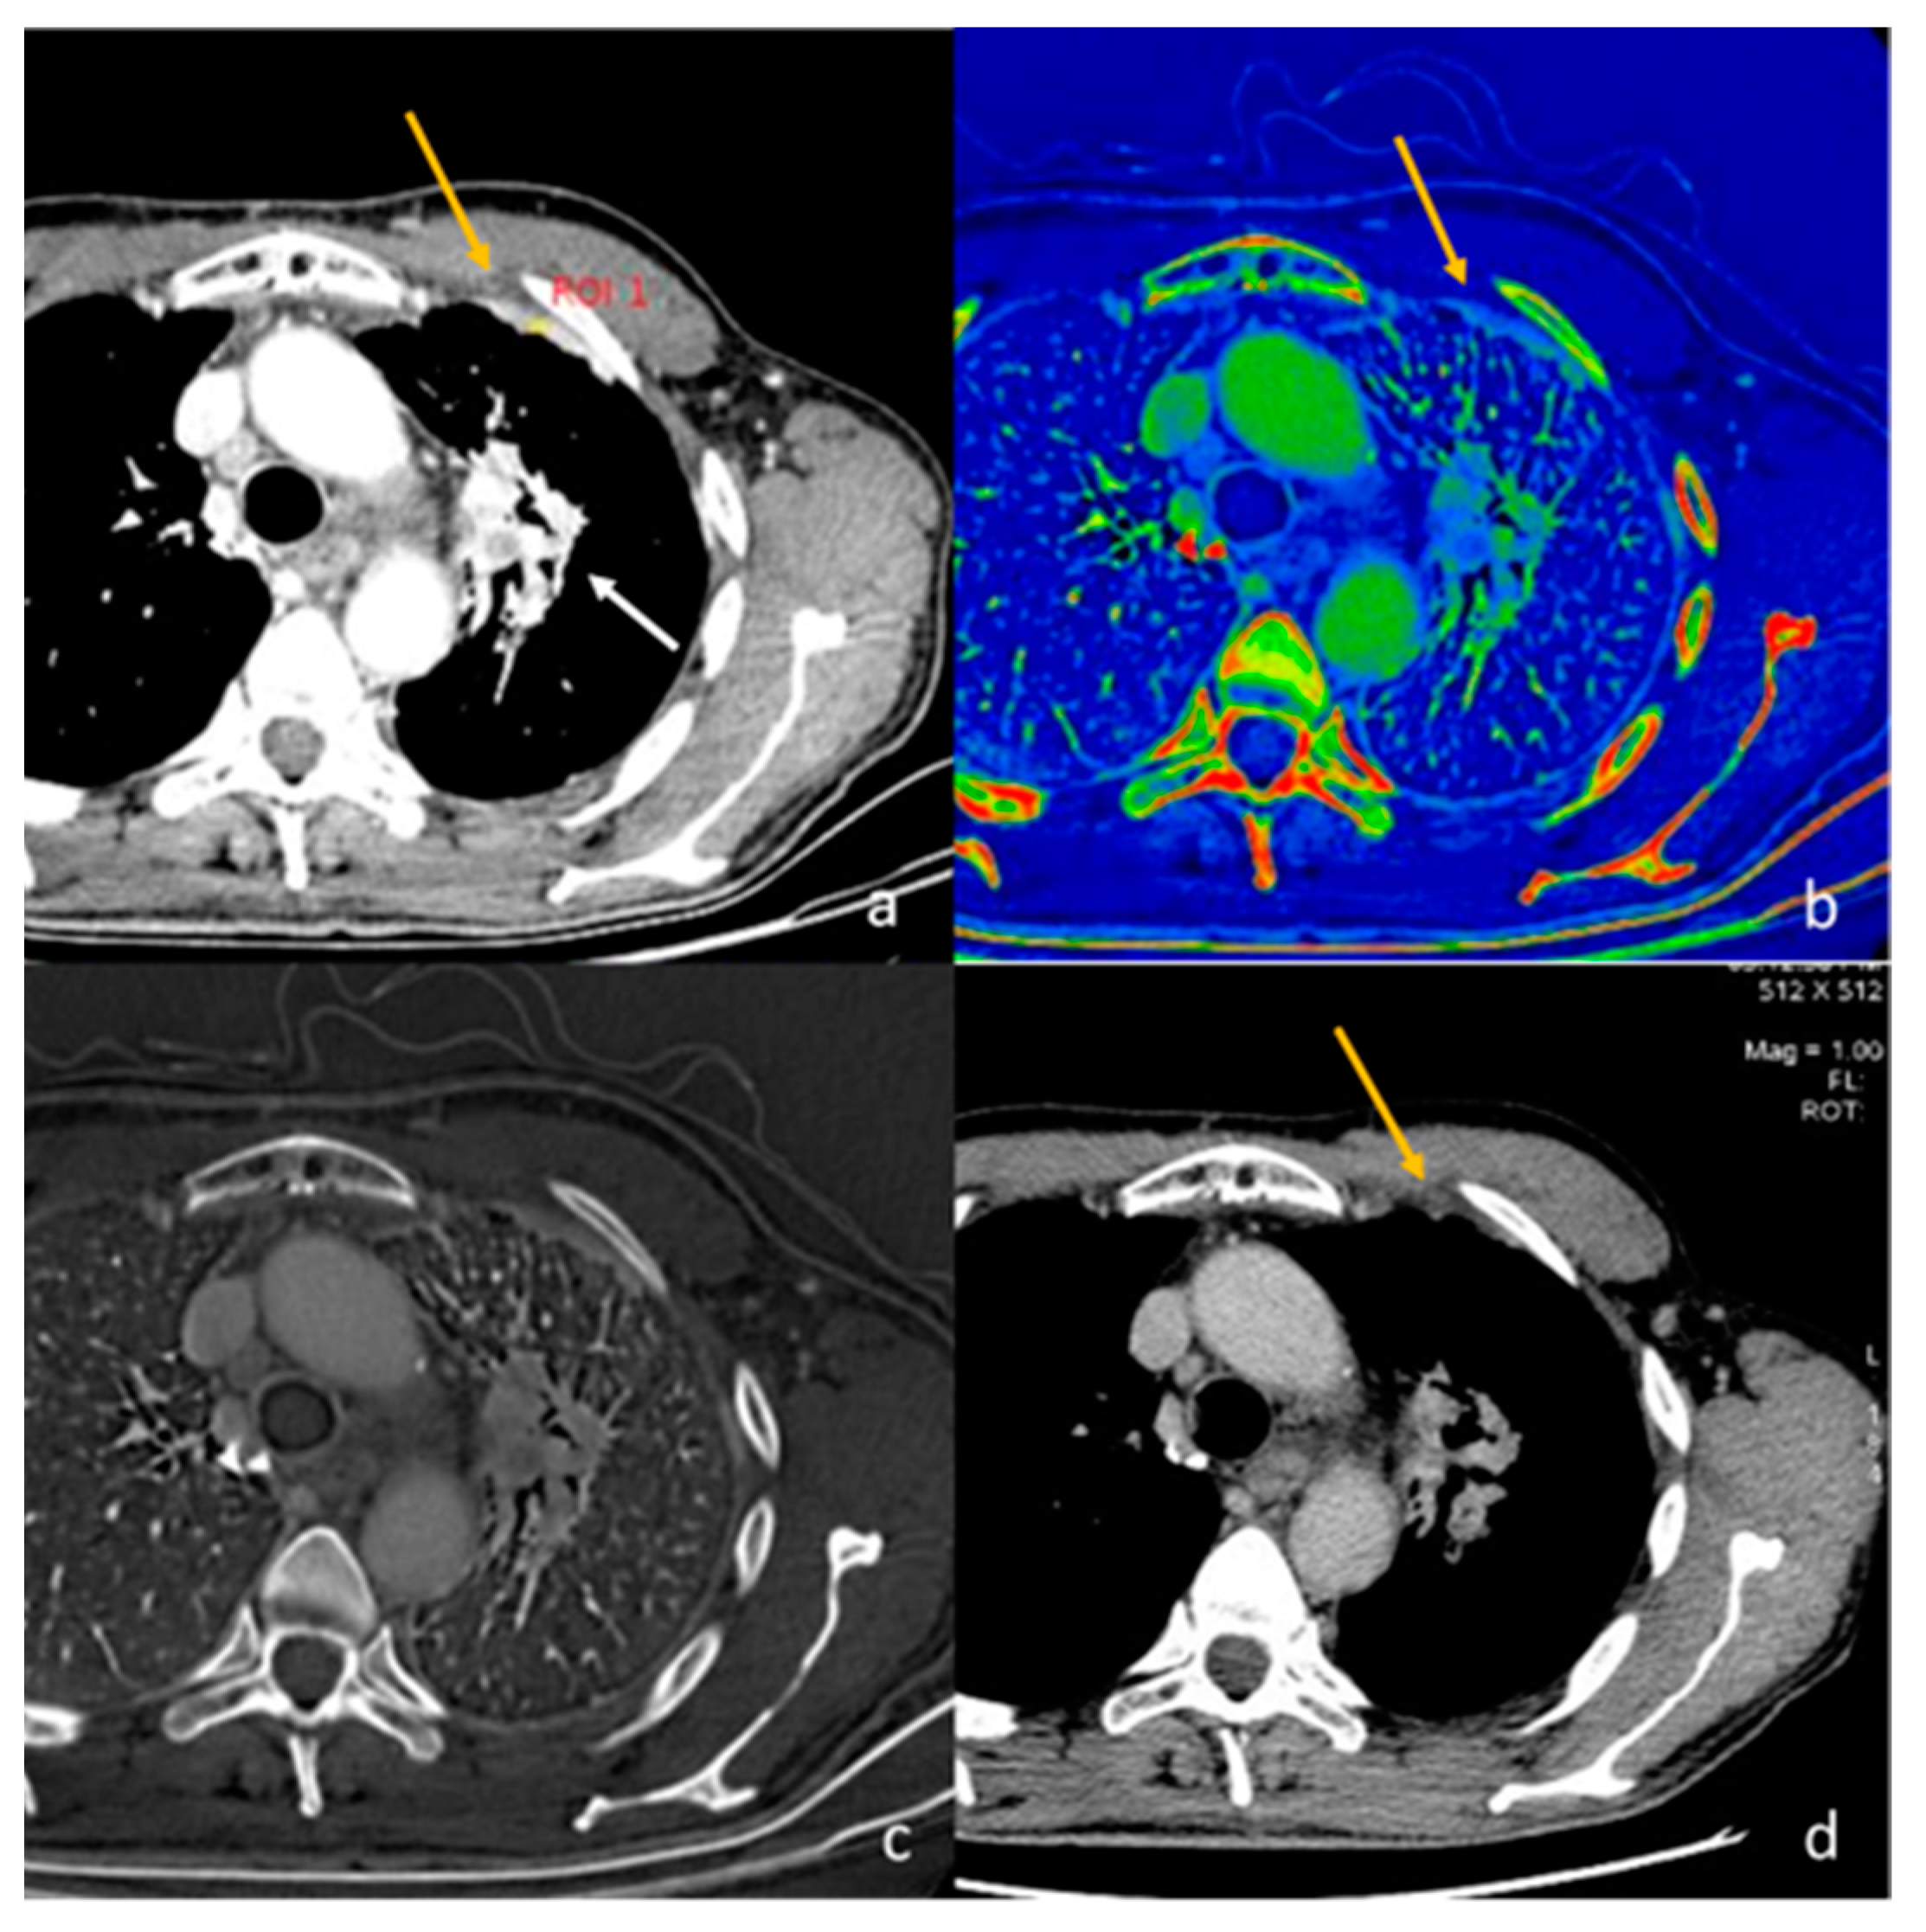

- Lennartz, S.; Le Blanc, M.; Zopfs, D.; Hokamp, N.G.; Abdullayev, N.; Laukamp, K.R.; Haneder, S.; Borggrefe, J.; Maintz, D.; Persigehl, T. Dual-Energy CT-derived Iodine Maps: Use in Assessing Pleural Carcinomatosis. Radiology 2019, 290, 796–804. [Google Scholar] [CrossRef]

| Sato et al. [48] Retrospective study | Japan | To compare the utility of ringlike peripheral increased IC and conventional findings for differentiating primary lung cancers from pulmonary metastases on DECT | 93 | Discovery CT750 HD or Revolution HD, GE Healthcare. No C.I. | Ringlike peripheral high IC had excellent interobserver agreement and high specificity (but poor sensitivity) for differentiating pulmonary metastasis from primary lung cancer and was independently predictive of pulmonary metastasis. |